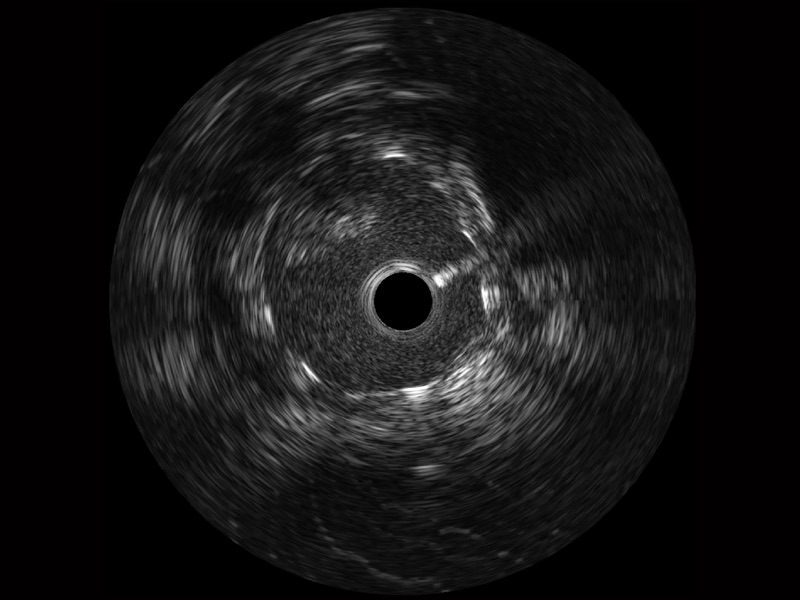

诸侯快讯官网宽频IVUS图像

对比传统IVUS导管成像,诸侯快讯官网宽频IVUS图像的近场支架梁显影更细腻,远场中膜外血管仍清晰可辨,兼顾远中近,兼顾分辨力与穿透深度